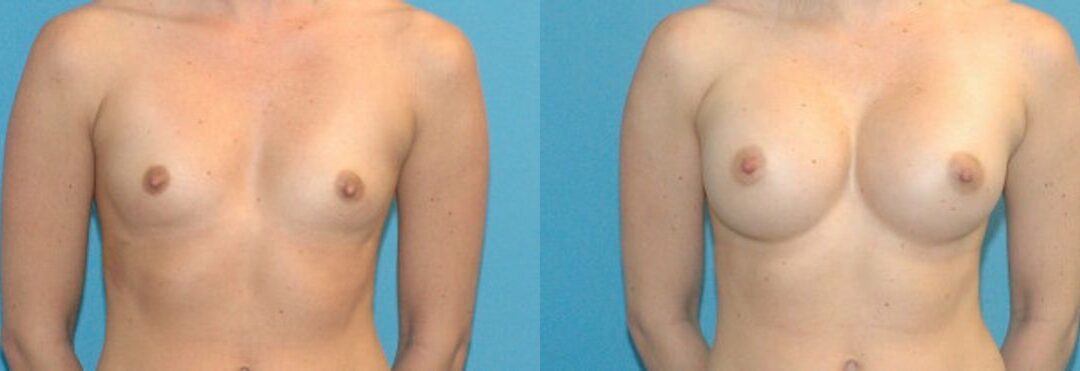

This 23 year old female dislikes the low profile appearnace of her breast shape. A 295 cc smooth round silicone implant was placed using a dual-plane technique. The result is a natural appearance along the upper pole of each breast and a rounder shape with more projection. She is delighted with her new look.